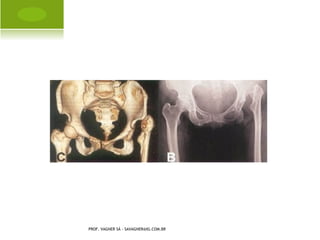

D ISPLASIA DO QUADRIL

PROF. VAGNER SÁ - SAVAGNER@IG.COM.BR

Í NDICE A CETABULAR